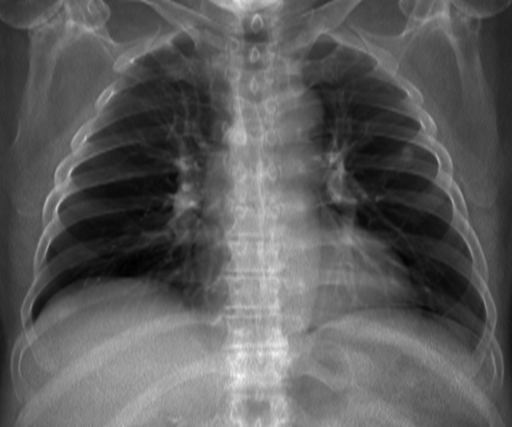

3.3 Applicability to Real X-ray

In order to explore the applicability of our algorithm to real X-ray and to examine whether the enhancement scheme introduces artifacts detrimental to CAD detection performance, we chose to perform the lung enhancement algorithm as a preprocessing step on nodule and mass CAD input images.

To accomplish this, we trained and tested a CheXNet [5] based network on 67,313 images released in ChestX-ray14 dataset(subset of PA images). In Figure 8 we show the results of the enhancement on an image from NIH ChestX-ray14 dataset [4]. The architecture we chose was a DenseNet-121 based network, with 512×512512512512\times 512 input size. Network weights were initialized with pretrained ImageNet weights and training was performed independently for enhanced images and non-enhanced images.

The dataset was split to 44,971 training, 11,245 validation and 11,097 test images. Results are given on the official test set in terms of average precision (AP) for the labels mass and nodule. We see a moderate increase in AP scores for the mass detection task (Table 2).

Refer to caption

(a)

(b)

(c)

(d)

Figure 8: Enhancement result on NIH ChestX-Ray14 image. One network was trained on the original X-ray and a second network was trained on the enhanced X-ray (a) Original X-ray (b) Enhanced X-ray (c) Zoom (d) Zoom -Enhanced